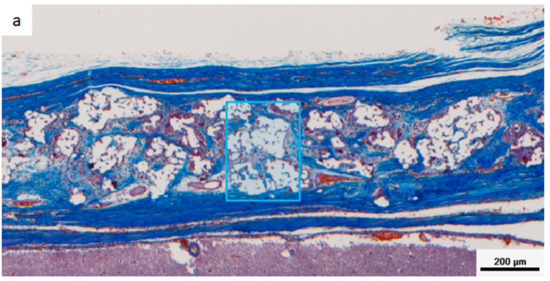

Figure 8 shows a multispectral image of MT-stained specimens in the CM and Sf-TCP groups. Aniline blue stains fibrous tissue blue, Masson liquid stains cells red, and Orange G stains blood cells orange. For quantitative analysis with inForm, CM and Sf-TCP existed in the bone defects.

Figure 8.

Masson’s trichrome (MT)-stained images taken with Vectra3. Aniline blue stains fibrous tissue blue, Masson liquid stains cells red, and Orange G stains blood cells orange. (a) CM implant at 4 weeks. (b) Sf-TCP implant at 4 weeks. The blue boxes indicate the area quantified in Figure 10.

Figure 9 shows an enlarged image of the region selected in Figure 8 and an image obtained by analyzing the corresponding portion with inForm. Cells and fibrous substances existed mainly in the periphery of CM in the CM group at 4 and 8 weeks, whereas in the Sf-TCP group, cells and fibers entered into the pores of Sf-TCP.

Figure 10 shows the results of quantifying areas of fibrous tissues and cells. Fiber and cell areas in the CM and Sf-TCP groups were compared at 4 and 8 weeks. The results showed that the fiber mass was significantly larger in the Sf-TCP group than in the CM group at both 4 and 8 weeks. However, actual cell amount did not change significantly.